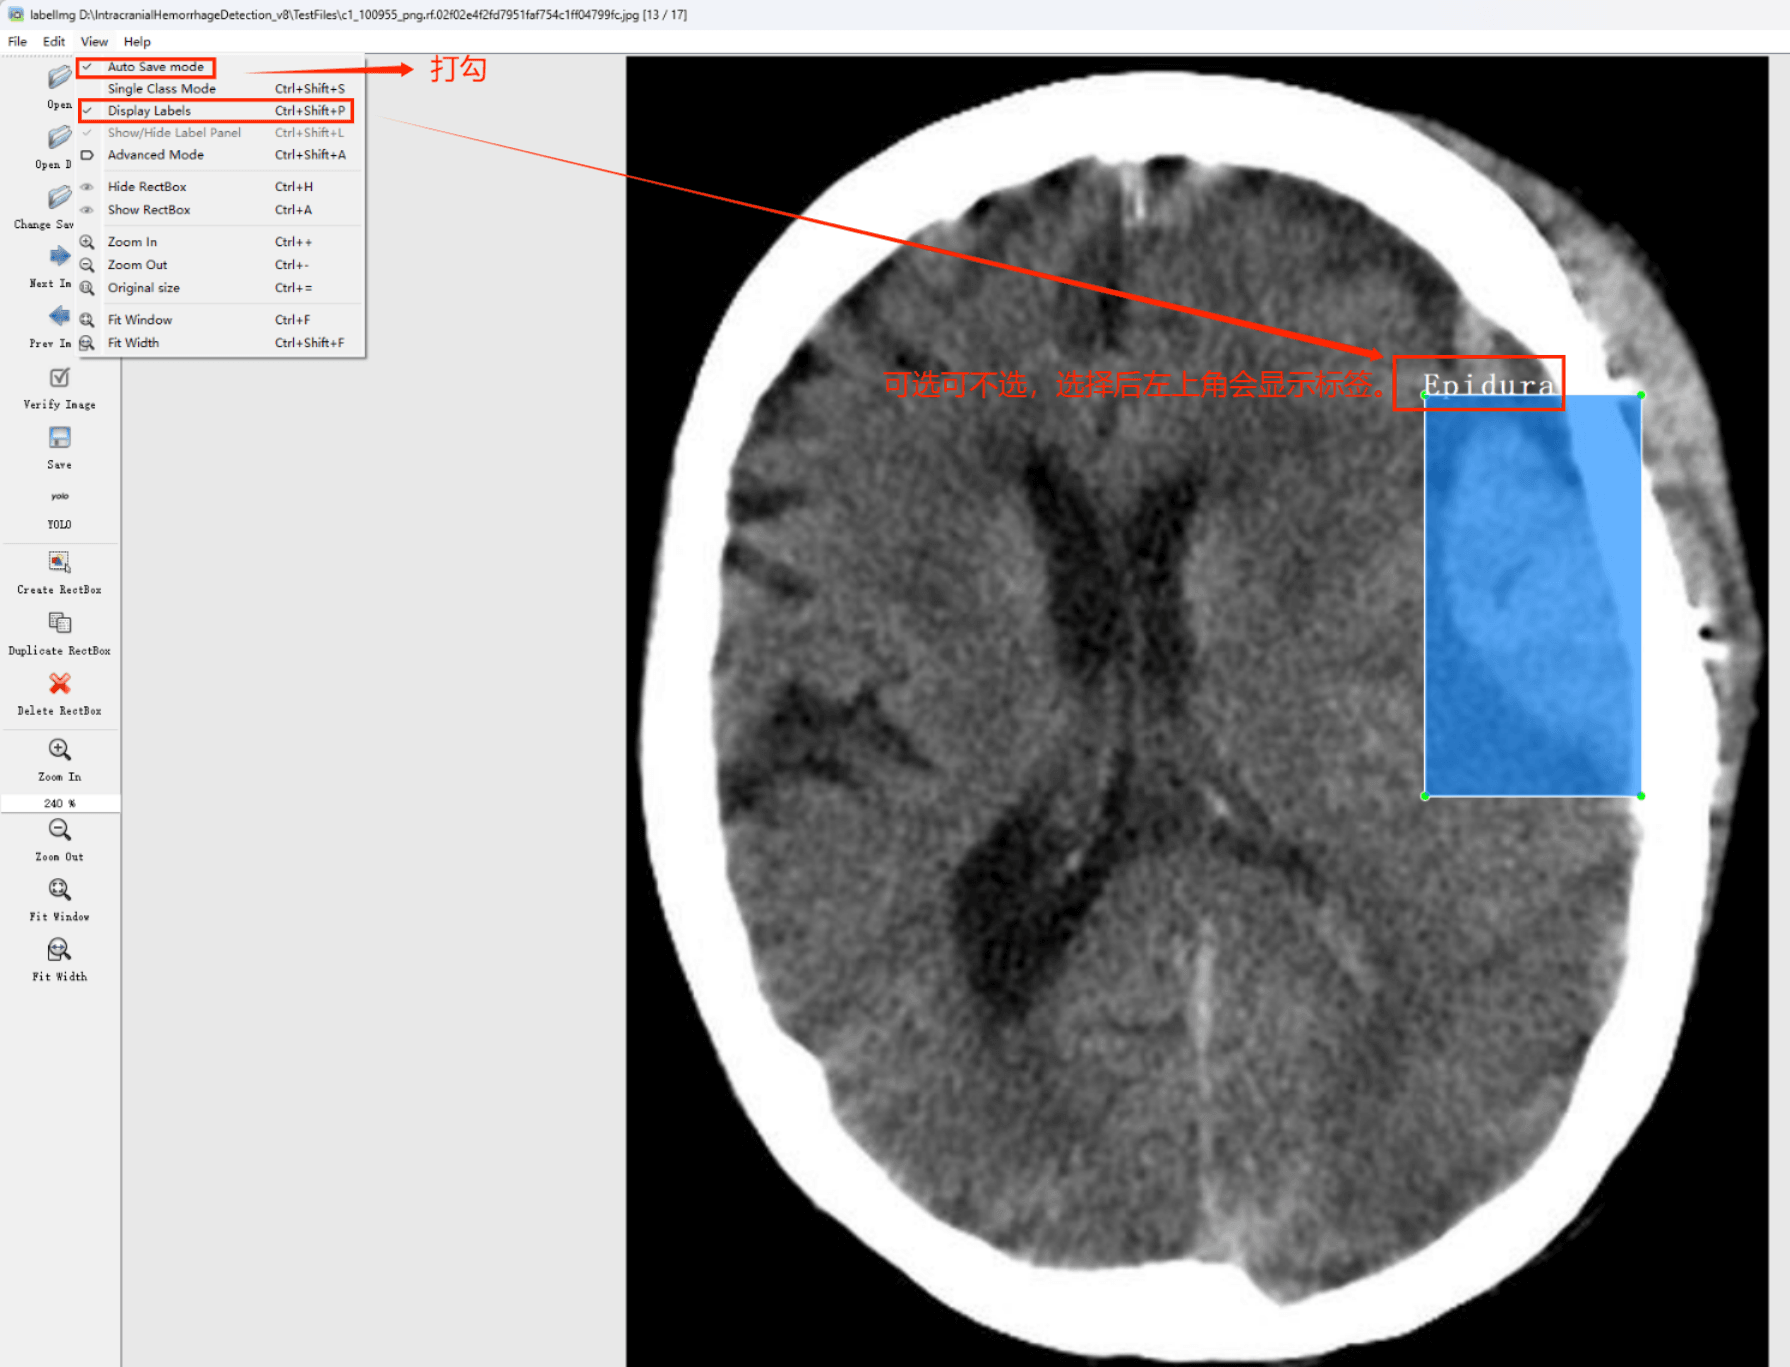

初识labelimg

打开后,我们自己设置一下

在View中勾选Auto Save mode

接下来我们打开需要标注的图片文件夹

指定标注文件存储的位置(如上图所示),开始执行标注流程。首先用矩形框选中目标区域,并对目标添加标签;随后切换至下一张图片继续操作。